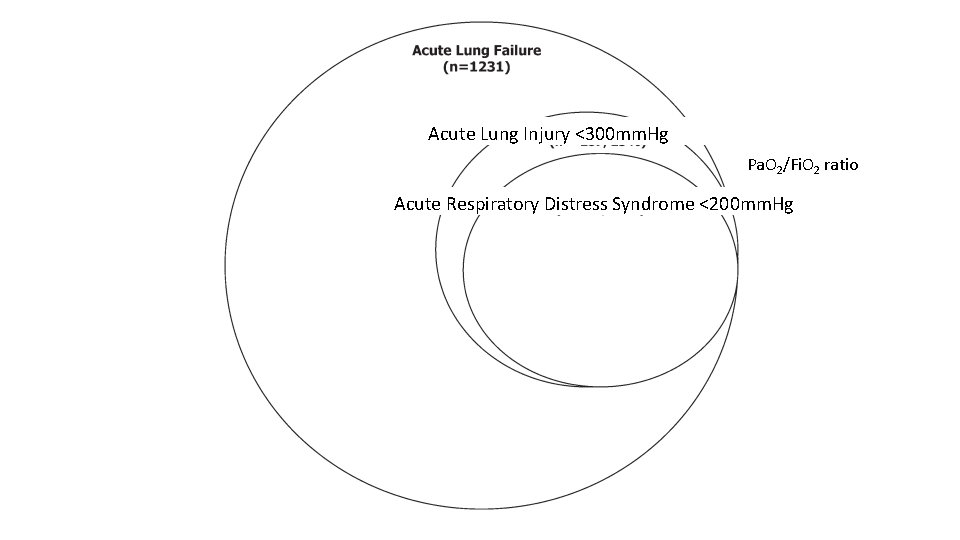

Acute Lung Injury <300 mm. Hg Pa. O 2/Fi. O 2 ratio Acute Respiratory Distress Syndrome <200 mm. Hg